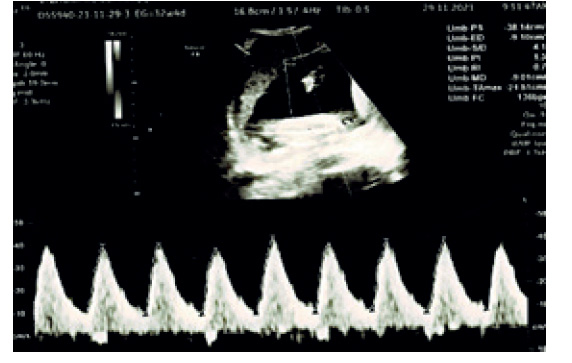

Al persistir las contracciones uterinas, se administró el tocolítico atosibán 7,5 mg/mL por dos ciclos vía endovenosa y se continuó con nifedipino (Adalat) 10 mg cada 8 horas por vía oral. También se prescribió progesterona 200 mg 2 óvulos vaginales hasta el final del embarazo. Para la maduración pulmonar se indicó betametasona 12 mg por vía intramuscular, por dos días en las semanas 24, 28 y 33. Para la protección neurológica se administró sulfato de magnesio 4 g por vía endovenosa. En las evaluaciones ecográficas realizadas cada 2 semanas se observó biometría y crecimiento fetal adecuado para la edad gestacional. El índice de líquido amniótico (ILA) y el Doppler de las arterias umbilicales y cerebral media fueron normales (figura 2). La valoración del bienestar fetal por cardiotocografía realizados diariamente y luego dos por semana, mostraron trazos reactivos.

Figura 2 ecografía doppler fetal de la arteria umbilical a las 32 semanas. el índice de pulsatilidad (ip) fue normal.